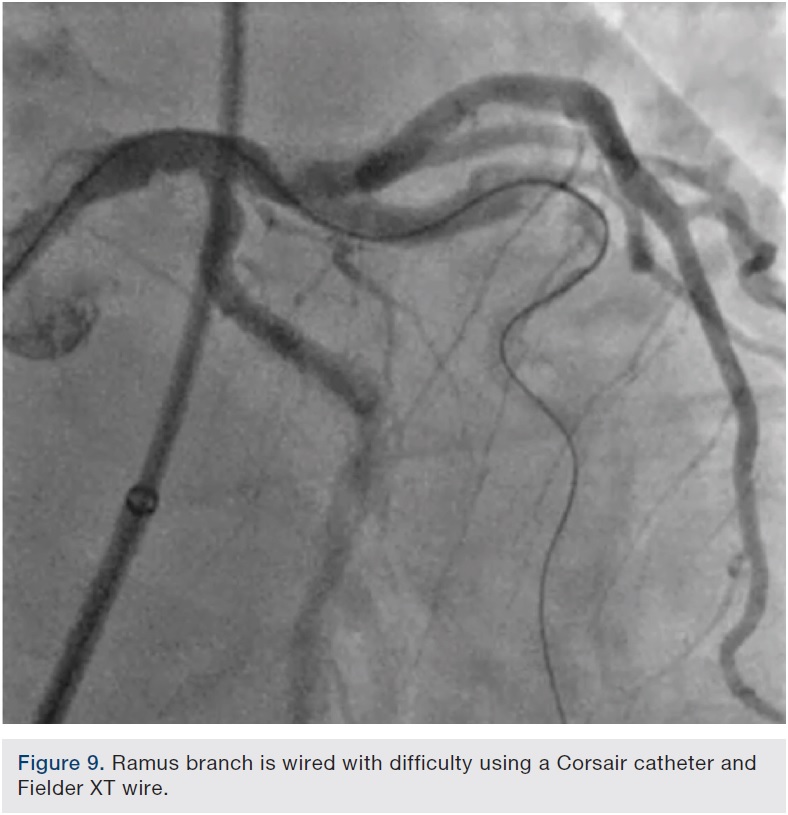

Angiography showed no obvious injury to the vessels and after rewiring and post dilating the proximal circumflex stent, attention was then turned to the ramus branch. This vessel had a highly tortuous, severely calcified critical stenosis. Wiring with Frontline wires (Asahi Intecc) was initially unsuccessful. Eventually, a combination of an Asahi Fielder XT wire (Abbott Vascular) and a Corsair catheter (Asahi Intecc) was used to traverse this lesion (Figure 9).